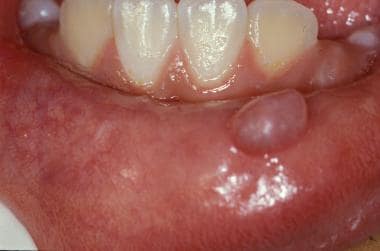

Chirurginės procedūros Chirurginės procedūros odontologijoje apima platų spektrą veiksmų, kurie gali būti reikalingi siekiant gydyti sudėtingus dantų, dantenų, žandikaulių ir burnos sutrikimus (cistų, gerybinių navikų, išdygusių ir neišdygusių dantų šalinimą, implantacijas, kaulo augmentacijos procedūra ir t.t).Burnos ir lūpų cistų, gerybinių navikų šalinimasRetinuotų, virškomplektinių ir kitų dantų bei dantų šaknų šalinimasLiežuvio pasaitėlio plastikaBurnos ir lūpų cistų, gerybinių navikų šalinimasTai chirurginė procedūra, kurios metu pašalinamos cistos, atsiradusios burnos ertmėje ar ant lūpų, bei kiti gerybiniai navikai (fibromos, papilomos, granulomos, lipomos ir pan.) susidarę kauluose arba minkštuosiuose audiniuose, dantų srityje.Cistose dažnai kaupiasi skysčiai, įskaitant pūlius, kurios dažnai susidaro dėl infekcijų, dantų traumų ar kitų priežasčių. Cistų šalinimas gali būti būtinas, siekiant išvengti aplinkinių audinių pažeidimį, infekcijos plitimo ar kaulo pažeidimo.Pradžioje cistos formavimasis dažnai būna nepastebimas, tačiau vėliau pasireiškia kaulo deformacija, patinimu ar net „skylučių“ dantenose atsiradimu, pro kurias išsiskiria pūliai. Dėl šios priežasties cistos dažniausiai nustatomos atsitiktinai, atliekant rentgeno tyrimus dėl kitų sveikatos problemų.Kodėl reikia pašalinti cistas ir auglius?Nors dauguma burnos ir lūpų cistų, mukocelių ir kitų formacijų yra gerybiniai augliai ir nesukelia pavojingų sveikatos problemų, jų pašalinimas gali būti būtinas dėl šių priežasčių:Estetinis diskomfortas: Dauguma pacientų pasirenka chirurginį gydymą dėl estetinių priežasčių, ypač jei formacijos atsiranda matomose vietose (pvz., ant lūpų).Funkciniai sutrikimai: Jei formacija trukdo valgymui, kalbėjimui arba sukelia skausmą, ją gali prireikti pašalinti.Infekcijos prevencija: Kai kurios cistos gali užkrėsti, sukelti uždegimus arba netgi galiausiai virsti piktybiniais navikais, todėl jų pašalinimas padeda išvengti šių komplikacijų.Augimas: Jei cista ar mukocelė auga ir sukelia spaudimą aplinkiniams audiniams, jos pašalinimas gali užkirsti kelią tolesniam pažeidimui.Retinuotų, virškomplektinių dantų ir šaknų šalinimas Tai chirurginė procedūra, kurios metu pašalinami dantys ar jų šaknys, kurios dėl įvairių priežasčių nepavyksta išdygti (išsiveržti) į burnos ertmę, lieka „užstrigusios” žandikaulio kauluose.Kada reikia pašalinti retinuotus ar virškomplektinius dantis?Dantis sukelia skausmą, infekciją ar uždegimą.Dantis sukelia gretimų dantų pažeidimus arba nelygų dantų išsidėstymą.Dantis sukelia cistų ar kitų uždegiminių formacijų susidarymą.Dantis kelia riziką dėl infekcijų (ypač kai jie dalinai prasiveržia ir jų apatinė dalis lieka uždara dantenose).Dantis nebeauga arba jo šalinimas gali pagerinti kitų dantų padėtį (pavyzdžiui, prieš ortodontinį gydymą).Dantų šalinimas yra būtinas, kai:Dantis sukelia skausmą, infekciją ar uždegimą.Dantis sukelia gretimų dantų pažeidimus arba nelygų dantų išsidėstymą.Dantis sukelia cistų ar kitų uždegiminių formacijų susidarymą.Dantis kelia riziką dėl infekcijų (ypač kai jie dalinai prasiveržia ir jų apatinė dalis lieka uždara dantenose).Dantis nebeauga arba jo šalinimas gali pagerinti kitų dantų padėtį (pavyzdžiui, prieš ortodontinį gydymą).Liežuvio ir lūpos pasaitėlio plastikaLiežuvio ir lūpos pasaitėliai (ang. tongue tie) yra maži gleivinės raiščiai, kurie jungia liežuvį su burnos dugnu (liežuvio pasaitėlis) ir viršutinės lūpos pusę su dantenomis (lūpos pasaitėlis). Kai liežuvio pasaitėlis yra per trumpas arba per stipriai įtemptas, tai gali sukelti problemų, pavyzdžiui, sunkumų kalbant ar valgant, arba sunkumų maitinant kūdikį.Jei lūpos pasaitėlis yra per žemas ar storas, jis gali trukdyti tinkamai susiformuoti tarpdančiams, sukelti tarpą tarp priekinių dantų (vadinamą diastema), trukdyti dantų protezavimui arba netgi sukelti kalbos problemų.Jei pasaitėlis trukdo kalbėjimui, valgymui ar kitoms kasdienėms funkcijoms, kartais gali prireikti chirurginio įsikišimo, kad būtų pašalinta dalis pasaitėlio. Tai paprastai yra greita ir nesudėtinga procedūra, vadinama frenotomija.Dažniausiai užduodami klausimai (D.U.K.)Ką daryti, jei įtariate cistą ar naviką?Jei pastebėjote, kad burnoje arba ant lūpų atsirado patinimas, gumbas ar nepaaiškinami skausmai, svarbu kuo greičiau kreiptis į specialistą. Gydytojas atliks išsamų tyrimą (dažnai tai būna biopsija ar ultragarsinis tyrimas) ir pasiūlys geriausią gydymo metodą, priklausomai nuo naviko tipo ir dydžio.Į kurį specialistą kreiptis, jei pajutau burnoje gumbą ar skausmą?Burnos chirurgai ir veido bei žandikaulių specialistai turi didelę patirtį sprendžiant šias ar panašias problemas, todėl pirmiausia reikėtų kreiptis konsultacijai ir detaliasniam ištyrimuiAr danties šalinimas yra skausminga procedūra?Danties šalinimas (ekstrakcija) yra dažna odontologinė procedūra. Dažnu atveju atliekant danties šalinimą, pacientai patiria tik minimalų diskomfortą, nes procedūros metu naudojamos vietinės anestezijos priemonės. Tačiau, kaip ir su bet kokia chirurgine procedūra, kiekvienas žmogus gali jausti skirtingą skausmą ir diskomfortą priklausomai nuo danties būklės ir sudėtingumo.Kodėl reikia pašalinti cistas ir auglius?Nors dauguma burnos ir lūpų cistų, mukocelių ir kiti dariniai yra gerybiniai augliai ir nesukelia pavojingų sveikatos problemų, jų pašalinimas gali būti būtinas dėl šių priežasčių: jei trukdo valgymui, kalbėjimui arba sukelia skausmą, dėl infekcijos plitimo bei augimo bei dėl estetinių priežasčių.Kodėl atsiranda liežuvio pasaitėlio patologija?Liežuvio pasaitėlio patologija dažnai yra įgimta būklė, kurią gali sukelti genetiniai faktoriai arba netinkamas burnos vystymasis. Tai gali sukelti kalbos, maitinimo ir burnos higienos problemas. Chirurginis gydymas gali būti veiksmingas būdas, siekiant pašalinti šias problemas ir pagerinti gyvenimo kokybę. Svarbu pasitarti su specialistu, jei pastebite, kad liežuvio judėjimas yra ribotas arba yra sunkumų kalbant ar valgant.Kaip atliekama retinuotų dantų šalinimo procedūra?Dantų šalinimas yra sudėtinga chirurginė procedūra, kuri dažnai atliekama vietinėje anestezijoje. Kai kuriais atvejais, jei dantis labai gilus ar sunkiai prieinamas, gali prireikti bendrosios nejautros.Registruokitės šiai paslaugai dabar Internetu +370 444 77777 Paslaugos specialistai Visi Kaunas Vilkaviškis Visi specialistai Shahaf Givony Gyd. burnos chirurgasKaunas Rasa Pedišienė Gyd. burnos chirurgėKaunas, Vilnius Justinas Bardijevskis Implantuojantis ir protezuojantis gyd. odontologasKaunas, Vilkaviškis Gabrielė Berniūtė Gyd. odontologė, specializuojasi dantų šalinimeKaunas Otilija Lieščinskaitė Gyd. odontologė, specializuojasi dantų šalinimeKaunas Greta Milvydaitė Gyd. odontologė, specializuojasi dantų šalinimeVilkaviškis Shahaf Givony Gyd. burnos chirurgasKaunas Rasa Pedišienė Gyd. burnos chirurgėKaunas, Vilnius Justinas Bardijevskis Implantuojantis ir protezuojantis gyd. odontologasKaunas, Vilkaviškis Gabrielė Berniūtė Gyd. odontologė, specializuojasi dantų šalinimeKaunas Otilija Lieščinskaitė Gyd. odontologė, specializuojasi dantų šalinimeKaunas Justinas Bardijevskis Implantuojantis ir protezuojantis gyd. odontologasKaunas, Vilkaviškis Greta Milvydaitė Gyd. odontologė, specializuojasi dantų šalinimeVilkaviškis